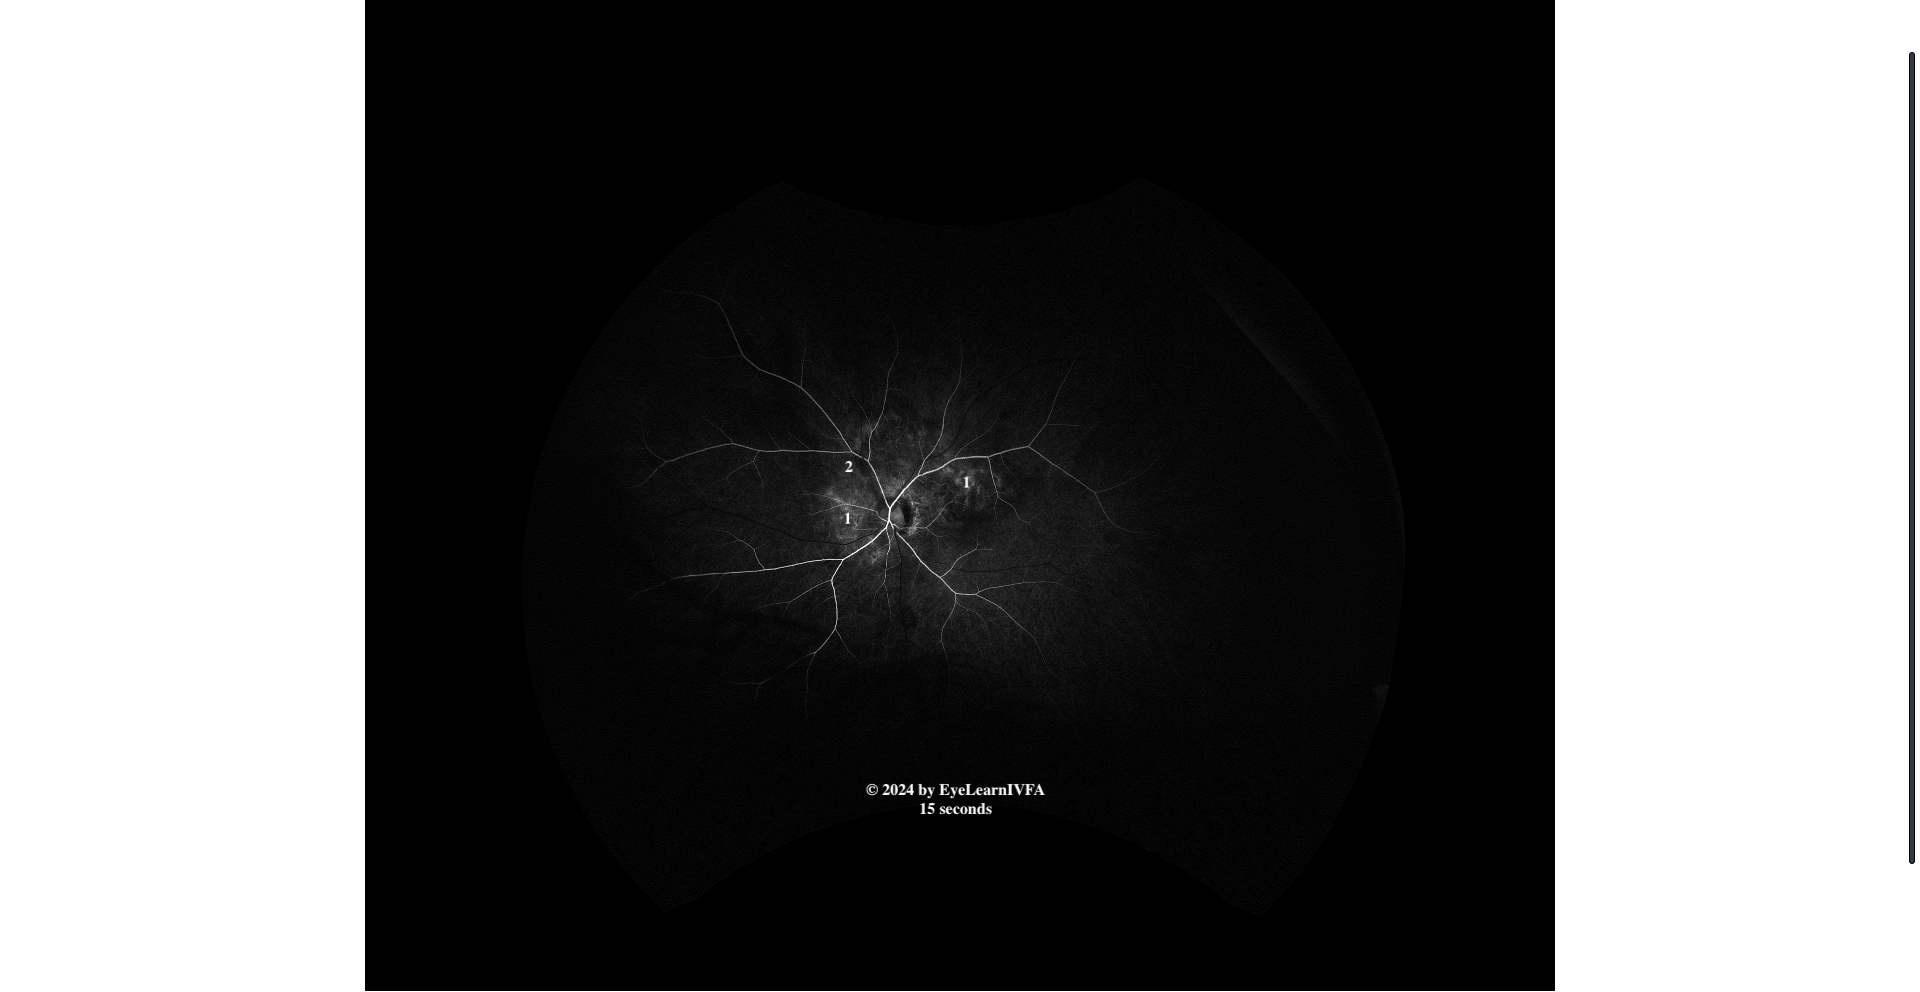

• IVFA OS at 15 seconds

Arterial phase

Key features include:

• Irregular, ill-defined patchy areas of hyper-fluorescence (1) and hypofluorescence (2) in a peripapillary disruption.